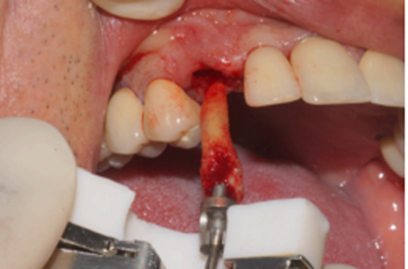

Figura 4 – Exodontia atraumática

O caso clínico a seguir irá descrever o sucesso dessa nova realidade. Paciente J.C., de 65 anos de idade, do sexo masculino, compareceu em minha clínica com o elemento 13 fraturado (Figura 1). Após análise criteriosa da tomografia, foi planejada a exodontia e a instalação imediata do implante seguindo as novas tendências no posicionamento tridimensional, isto é, a melhor posição no rebordo na relação dento alveolar (Figura 2). Foi realizada a terapia medicamentosa com a administração de Amoxicilina 500 mg, de oito em oito horas durante sete dias, iniciando um dia antes do procedimento, e o uso de anti-inflamatório após a cirurgia, durante três dias. A exodontia foi realizada de forma atraumática, como sugerido na literarura (Figuras 3 e 4) e foi realizada a fresagem para a instalação de um implante Due Cone Implacil De Bortoli (conexão morse) de 3.5 x 13 mm, que foi estabilizado a 46 Ncm (Figuras 5, 6 e 7). Após a instalação, o gap foi preenchido com biomaterial, um cicatrizador de 5.5 X 3.5 mm (diâmetro/altura) foi instalado e o tecido foi suturado ao seu redor, protegendo assim o biomaterial (Figura 8).